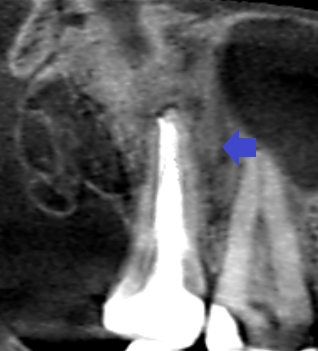

精密根管治療6ヶ月後の経過観察時の上顎第二大臼歯の矢状断のCT画像です。口蓋根の周りにみられた膿の影が消失し、歯槽骨が再生しています。